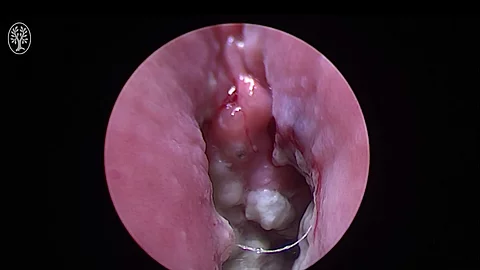

Cystoskopie, DJ-Entfernung (27.04.2023)

• 27.04.2023

• 00:11:48